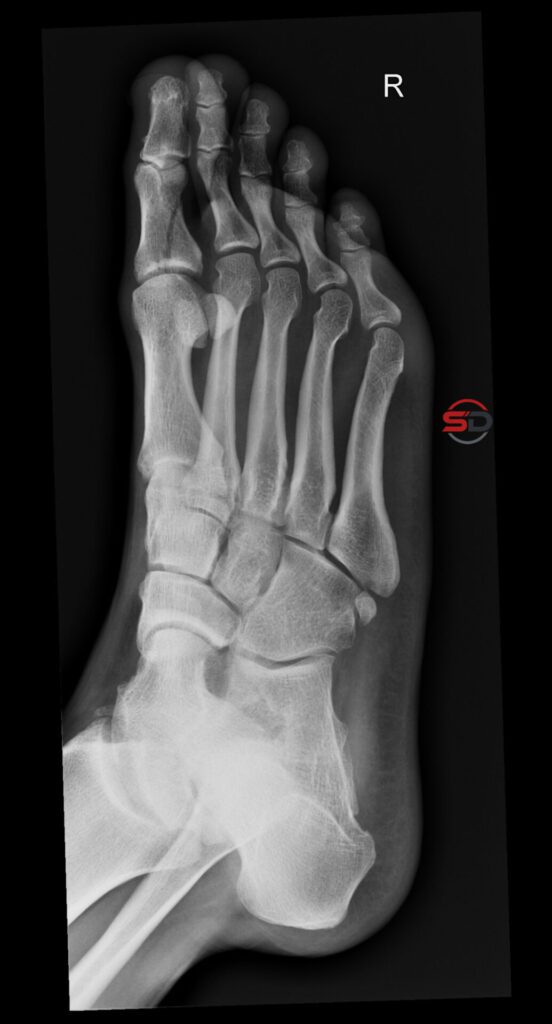

Akzessorische Knöchelchen: Wenn die Synchondrose zum Problem wird

Akzessorische Knöchelchen: Wenn die Synchondrose zum Problem wird Akzessorische Knöchelchen sind eine häufige Normvariante am Fuss und am oberen Sprunggelenk. […]